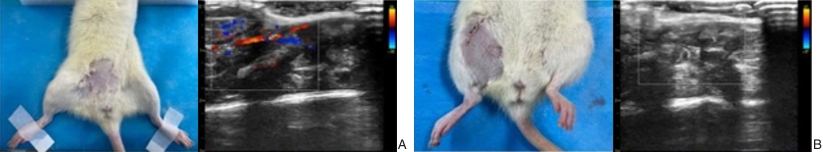

图1 建模及超声检查 A:假手术;B:下肢IRI模型Fig.1